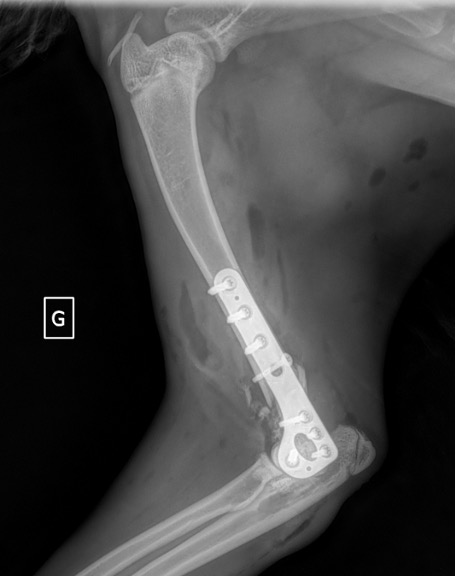

Exemple 2 :

Figure 4 : Pré-Op

Figure 5 : Post-Op Immédiat

Figure 6 : Post-Op 1 mois

Figure 7 : Post-Op 2 mois

Notre préférence va vers le placement de deux plaques humérales : une médiale de la plus grande taille possible et l’autre latérale, généralement d’une taille inférieure à la première. Dans l’exemple 1 (chat européen), une plaque de 2 mm est utilisée médialement et une plaque de 1,5 mm latéralement. Dans l’exemple 2 (chien Malinois), une plaque de 3,5 mm est utilisée médialement et une plaque de 2,7 mm latéralement.